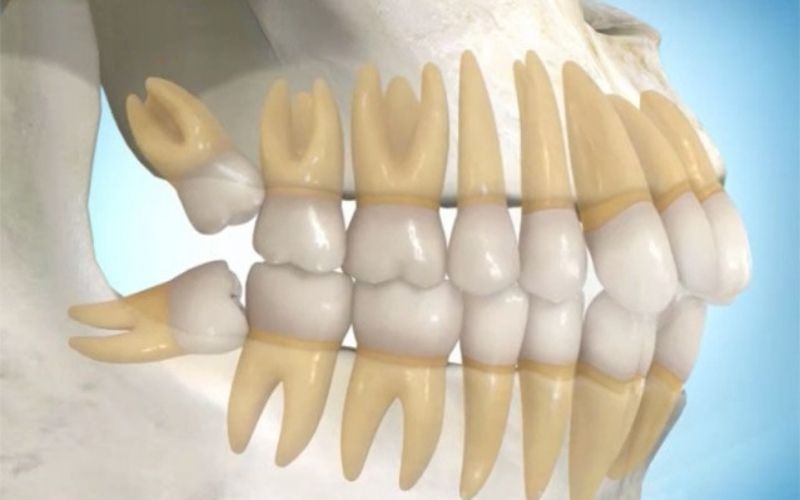

Gömülü Dişler

Sürmeyen dişler enfeksiyon, çürük, kist riski taşıyabilir; cerrahiyle çıkarılır, sonrasında bakım ve dinlenme önemlidir.